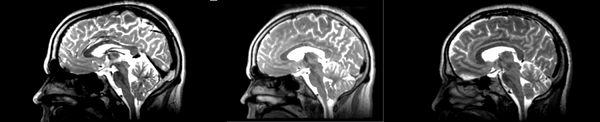

Register Images module

Initial

01053>01031_RI_initial.png - looks like the original 01053 image, but shifted, which is expected. resolultion a little worse.

Rigid

01053>01031_RI_rigid.png - center ventricles are mostly aligned, but not perfectly. in axial view, brain is more crooked than in initial scan... especially in frontal lobe.

Affine

01053>01031_RI_affine.png - ventricles aligned well. sizing decent. looks how one would expect affine to look. not perfect subcortically. some distortion, esp in temporal lobe.

B-spline

01053>01031_RI_bspline.png - good result. ventricles aligned well, but temporal lobe size is not the same as the target image.

Pipe Rigid

01053>01031_RI_pipe_rigid.png - shifted version of the original image. decent registration in the ventricles.

Pipe Affine

01053>01031_RI_pipe_affine.png - decent coreg. a bit of distortion in the frontal and temporal lobes, esp around the corpus collosum.

pipe B-spline

01053>01031_RI_pipe_bspline.png - good coregistration, but pretty blurred. also, I would have expected the temporal lobe to be coregistered better.